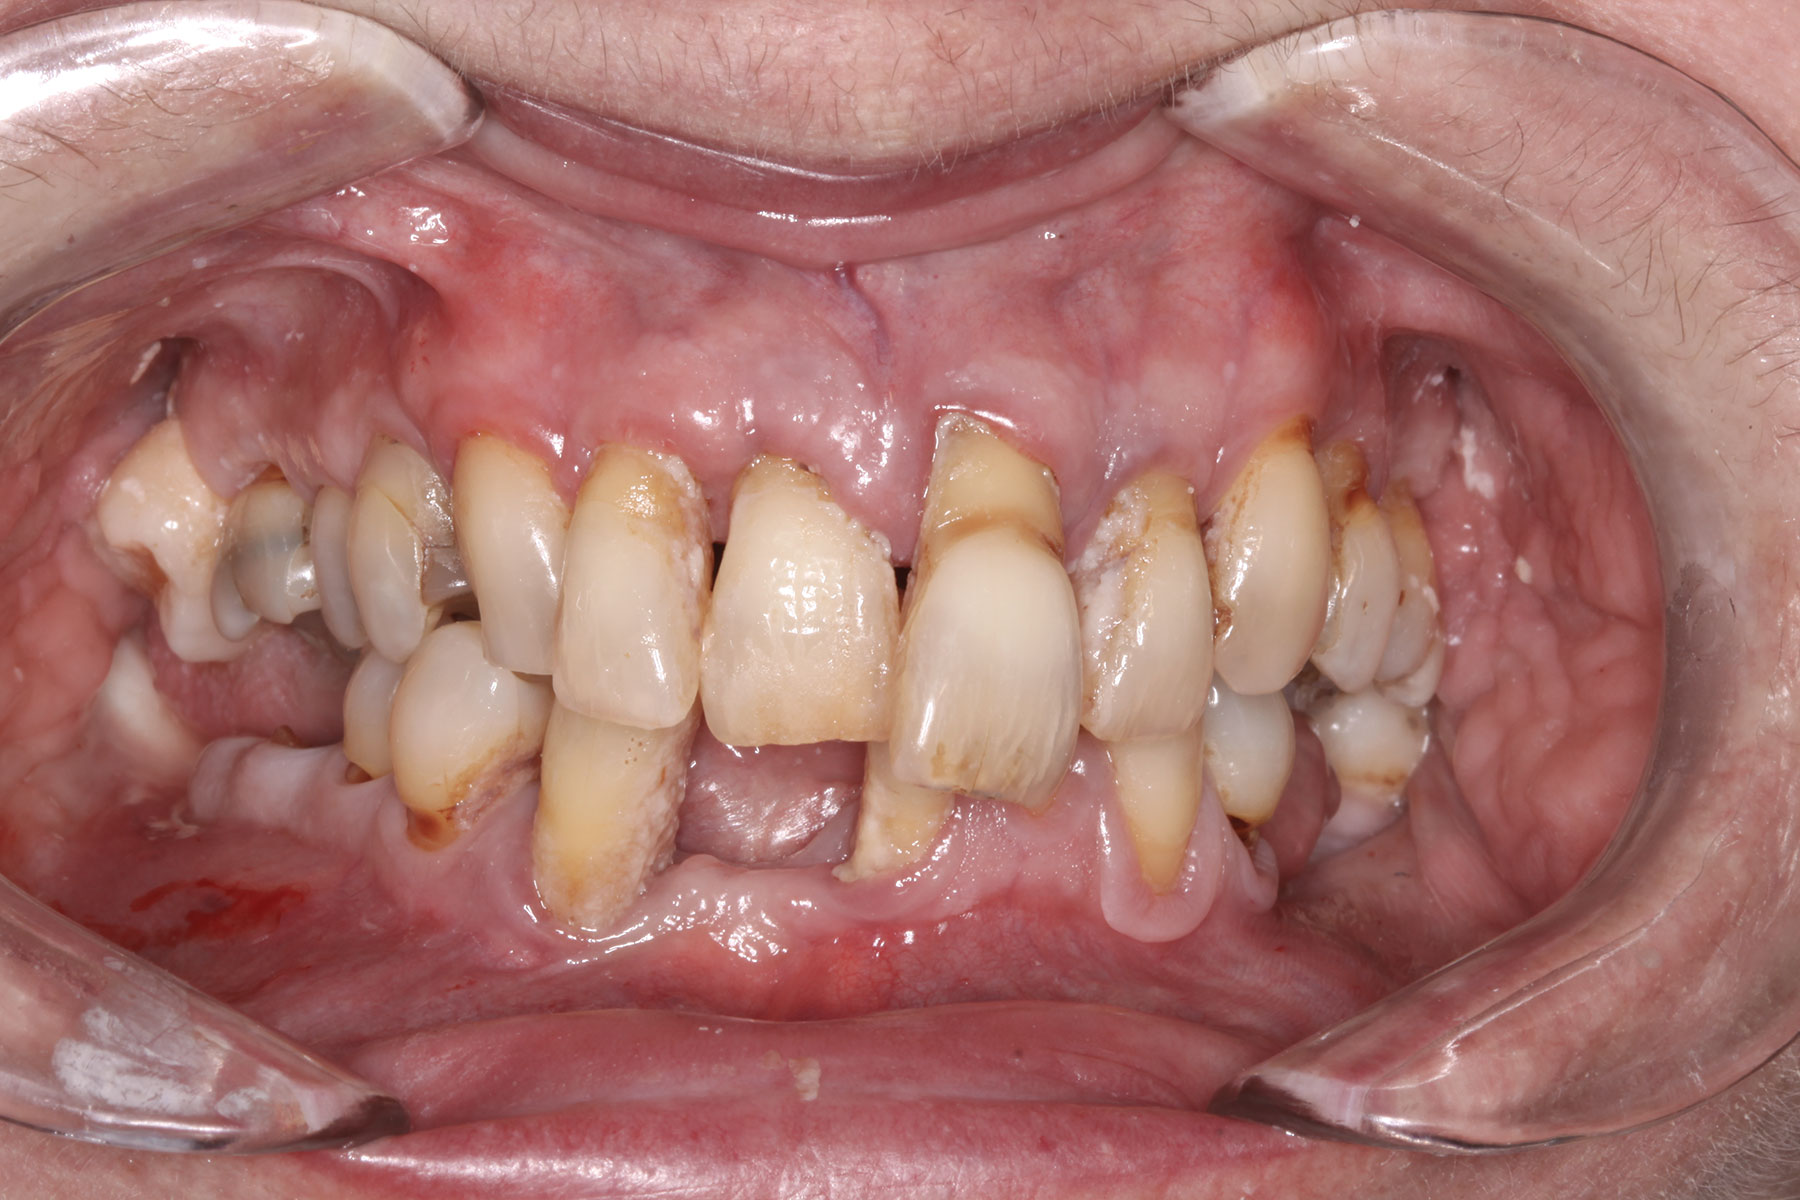

A 36-year-old male patient presented with a highly compromised maxillary dentition comprised of only teeth Nos. 4, 6, 7, 9, 10, 11, and 14 (Figure 1 and Figure 2). This poor condition was the result of only sporadic dental care with extractions and no teeth replacements. Soft tissues had normal contour, and bone profiles were generally sustained and favorable. The patient was excited about having the option to transform his compromised esthetics and function in one visit.

Fig 1. Case 1: Initial presentation for maxillary immediate implant, immediate load provisional restoration. Full-face photograph.

Fig 2. Initial presentation, intraoral view.